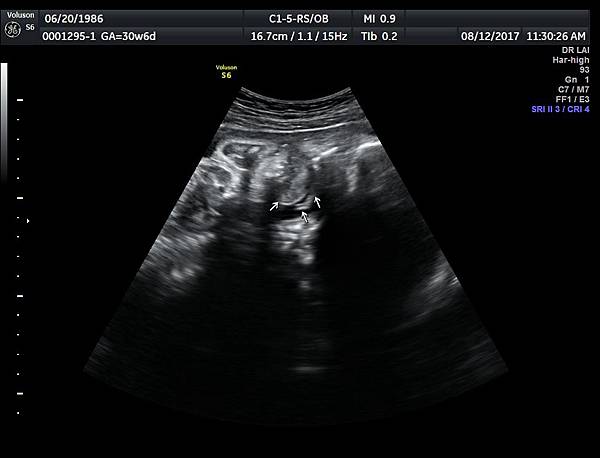

2017年8月12日一位22歲第二胎的孕婦在診所接受胎兒高層次及心臟超音波檢查,她說因為第一胎沒有兔唇但是顎裂,上網搜尋相關資訊所以來到診所安排檢查:她知道我會看懸雍垂(因為懸雍垂是軟顎最後形成的位置,如果看到完整懸雍垂,可以間接診斷正常的顎)

一個檢查如果要花很長的時間才能完成,這樣的檢查無法變成常規的篩檢方式,我已經在我的診所執行懸雍垂檢查一段時間,我檢查懸雍垂大約30 秒,前提是胎兒的臉最佳位置是側躺,其次是側躺偏向上,我的檢查步驟是上顎(含日後大門牙長出的位置)、舌頭、懸雍垂(= equal sign)(附圖1~8),如果超過60秒無法完成,只有兩個原因,一個是胎兒姿勢不適合或喉嚨羊水空間太小,這時候不要硬碰硬,只要先檢查其他部位,等待時機再回來即可,我的經驗是90%的cases都能順利完成這項檢查(肚皮厚的case真的是很難)。

有興趣的同業可以參考我的部落格備忘錄第119、120、127 及 236 這四篇,裡面有我做懸雍垂(uvula)的相關影像。